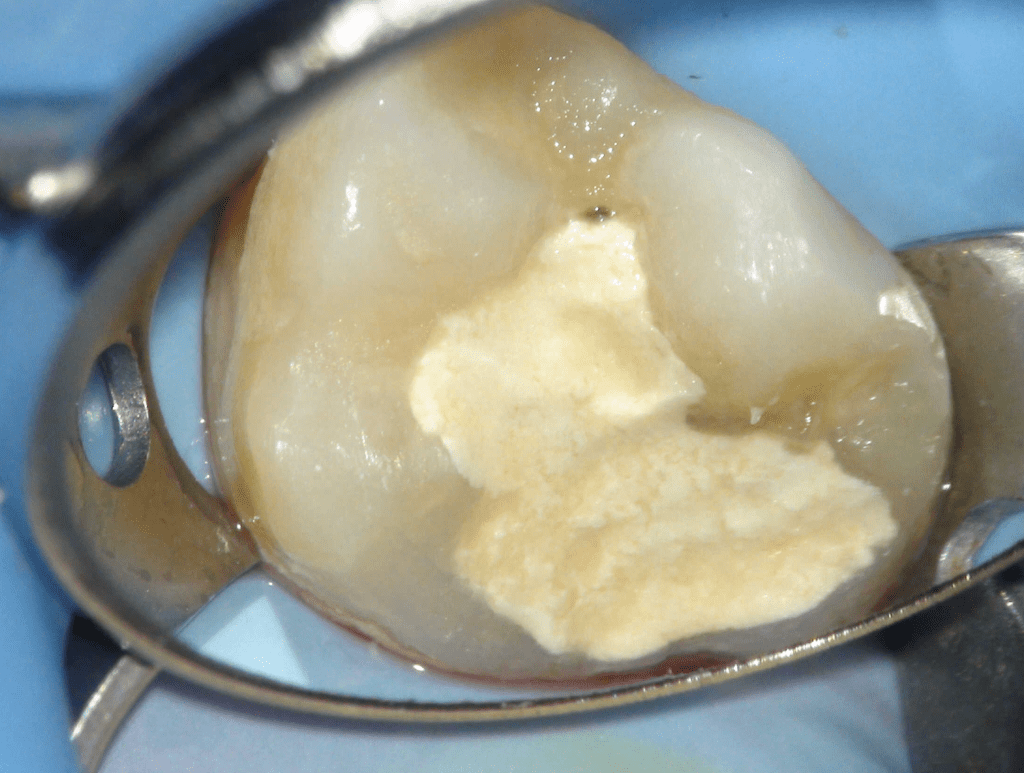

Reconstrucción preendodóntica

Reco pared vesticular

Reco preendo + 4 conductos molar superior